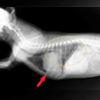

• 肺癌(肺腺癌)

◆シーズー 14歳8カ月 去勢オス 5.72㎏

◆稟告 食欲のムラ。たまに咳をする。